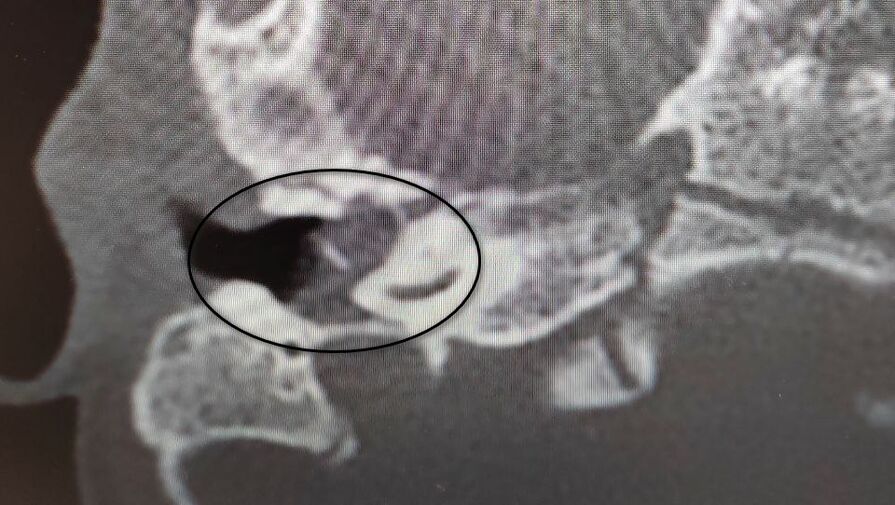

Девочка поступила в оториноларингологическое отделение больницы с хроническим гнойным средним отитом и подозрением на врожденную холестеатому барабанной полости — кистозное патологическое образование в среднем ухе. Врачи отметили, что подобное заболевание крайне редко диагностируется у детей в столь раннем возрасте.

«Холестеатома опасна тем, что может привести к рецидивирующему гноетечению и разрушению структур среднего уха, отвечающих за слух», — пояснили в пресс-службе ведомства.

После обследования и подтверждения диагноза пациентку направили на операцию, в ходе которой хирурги удалили у нее холестеатому, провели декомпрессию лицевого нерва и восстановили механизм звукопроведения.